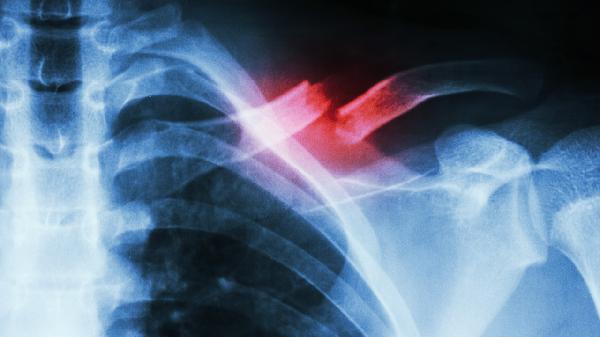

鎖骨骨折保守治療后一般需要4-6周開始逐步鍛煉,具體時(shí)間取決于骨折愈合情況、年齡、康復(fù)計(jì)劃、營(yíng)養(yǎng)狀態(tài)和并發(fā)癥等因素。

骨折線模糊是開始鍛煉的基礎(chǔ)指標(biāo),需通過X光確認(rèn)骨痂形成。臨床愈合通常需3-4周,此時(shí)可進(jìn)行被動(dòng)關(guān)節(jié)活動(dòng)。完全負(fù)重訓(xùn)練需等待骨性愈合,約需8-12周。